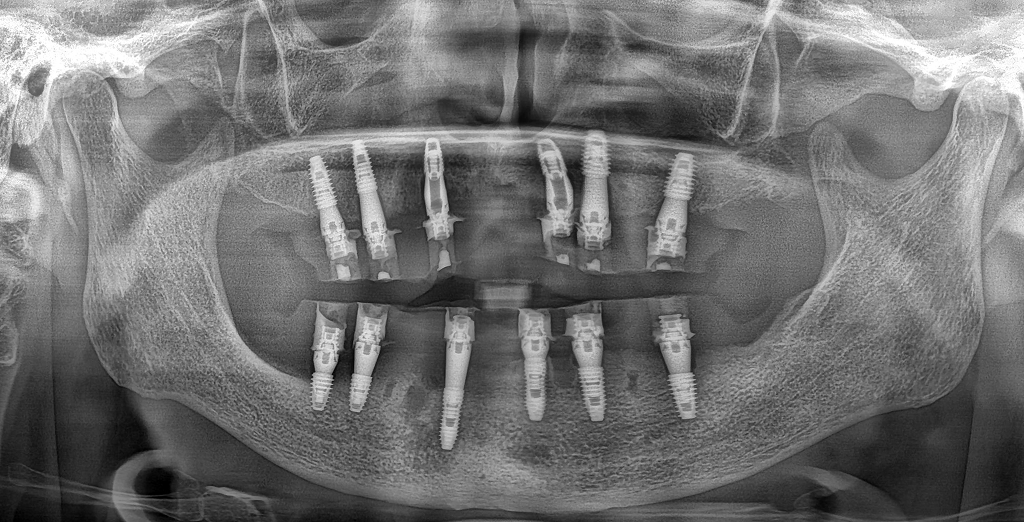

임플란트